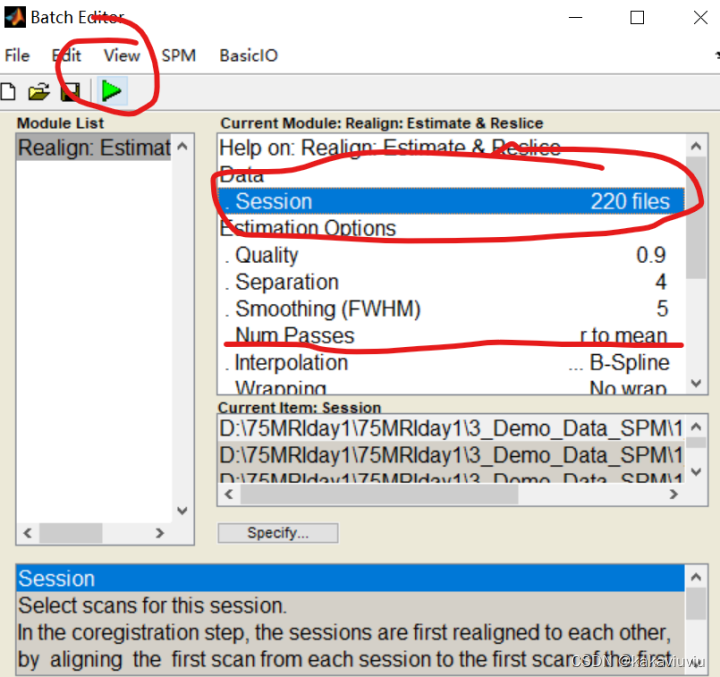

只筛选以a为开头的文件(上一步生成的时间校正后的文件)

文件选中就可以运行了。Num passes 后面的register to mean:选中to fist 与第一张图象对齐,to mean,就是与平均的对齐